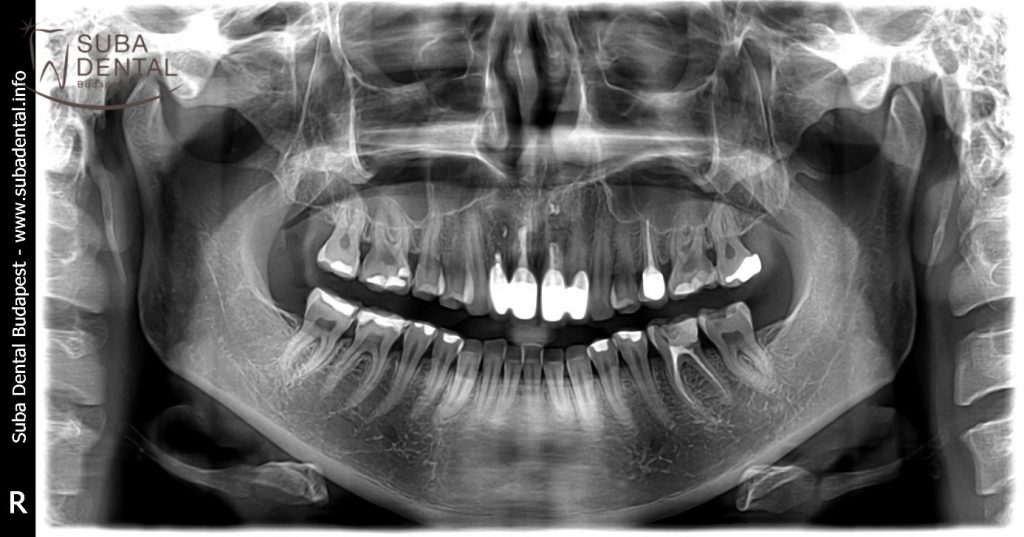

At the first encounter a panoramic radiograph and a series of photographs were taken of the teeth. The radiograph and the clinical examination of the mouth revealed that the upper left second premolar had chipped off, had to be root canal treated again and reinforced with a post-and-core abutment so that a crown could be securely mounted on it. The upper central incisors and the right lateral incisor had been root canal treated and had to be reinforced with a post-and-core abutment as well. The options were discussed with the patient and our choice fell on zirconia crowns for the upper incisors and the chipped-off premolar. Aesthetics can best be restored with metal-free E.Max crowns but since the teeth were root canal treated and had post-and-core abutments we opted for zirconia crowns rather than all-ceramic ones.

Panoramic radiograph of the initial condition

Follow-up panoramic radiograph of zirconia crowns mounted on natural teeth